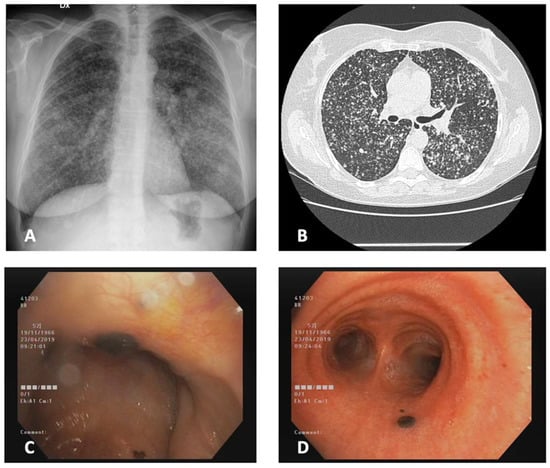

3.1. Case 1